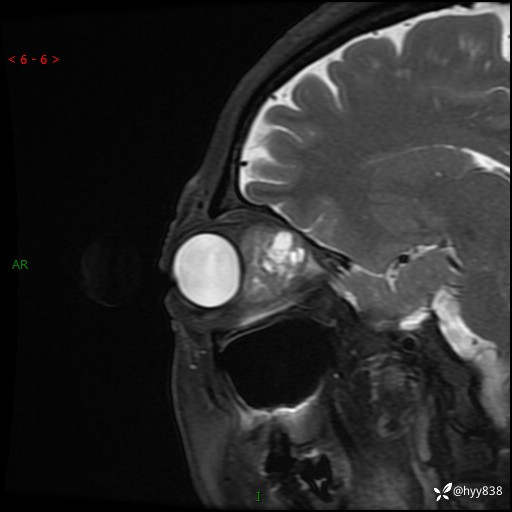

老年女性,右眼球突出1月。说说鉴别诊断,看谁第一个秒---(有结果)

主诉:发现右眼球突出1月余

简要病史:患者于1月前无明显诱因发现右眼球突出,偶感磨痛、眼胀,无视力下降,无头痛,恶心呕吐等不适。10天前就诊于当地县人民医院就诊,完善头颅ct检查,诊断为右侧眼眶肿物,建议患者上级医院进一步治疗,患者因个人原因拒绝。拟行手术,来我院就诊,门诊行相关检查后以“右眼眼眶肿物”收入院。 患病以来,患者精神饮食睡眠尚可,大小便如常、体重无明显改变。

辅助检查:MRI

临床诊断:眼眶肿物

眼眶MRI平扫+增强